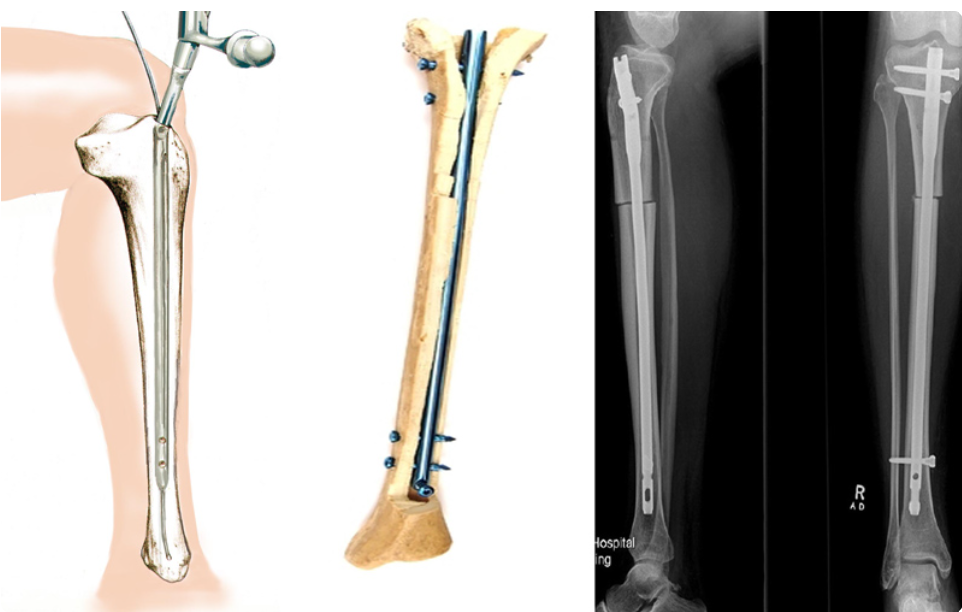

В случае перелома шейки бедра компания МосРентген Центр госпитализирует в Склиф для эндопротезирования.